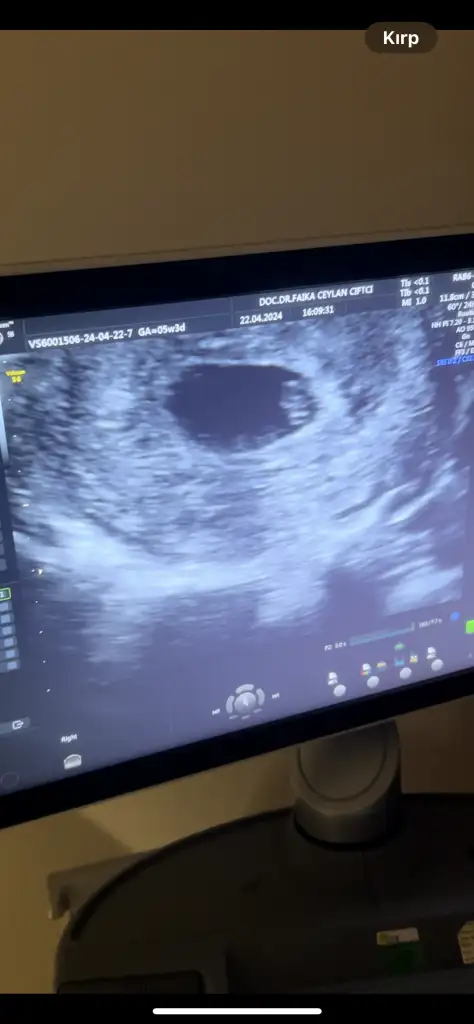

Bugün (6+3’te) şükürler olsun ilk kontrolümüze gidebildikKesemizi gördük, içinde de minik bir kelebeğin nabzı atıyordu tık tık Çok kısa da olsa dinletti doktorumuz

Bu da tüm teyzelerimize merhaba dediğimiz ilk ultrason fotomuz olarak dursun burada